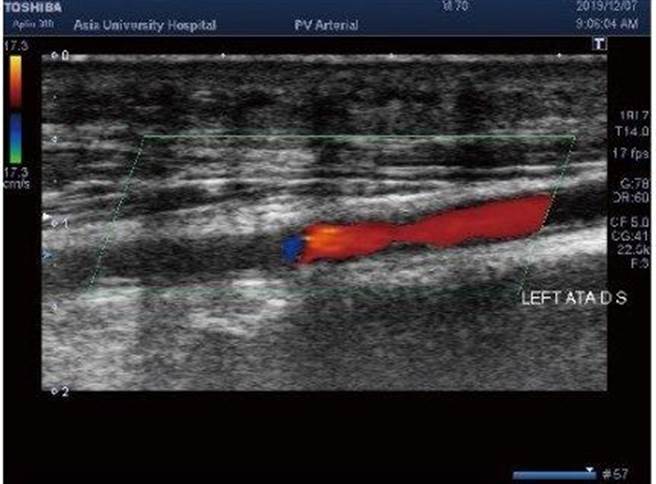

本身有糖尿病史的50岁张伯伯,因为左脚大拇指伤口迟迟未癒合,到亚大附医就医,肾臟科医师利用周边血管超音波检查,发现是左腿小腿动脉狭窄造成,转介心臟内科安排手术打通并稳定控制血糖后,伤口也逐渐康復中。

亚洲大学附属医院肾臟科主治医师陈虹志表示,张伯伯不仅有高血糖,本身也有高血压、高血脂病史,都容易引起血管钙化病变,所幸经周边血管超音波检查后,发现左股动脉血管内皮出现钙化,导致血管斑块、狭窄,紧急执行导管气球扩张后,改善下肢远端血循避免糖尿病足的发生。

血管超音波除了动脉检查之外,也常应用于静脉检查,特别是在肾臟科门诊常常会遇到下肢水肿患者,以往通常只能验肾功能、蛋白尿,儘量排除肾臟造成的因素,常常无法找出水肿原因;此时,超音波可以检查是否有静脉栓塞、三尖瓣逆流或下肢静脉瓣逆流等情形,再透过问诊来排除药物副作用、饮食不当等原因,对症下药治疗。

陈虹志提醒,血液透析患者的动静脉廔管就像是生命线一样,透过血管超音波评估透析廔管功能不佳的原因,像是动脉端狭窄、阻塞或静脉狭窄等,同时也能评估廔管成熟度以及血流量,在少数不易打针的透析患者身上,还能帮助调整下针位置、方向跟深度。

陈虹志建议,周边血管超音波具有非侵入性、不用注射显影剂等优点,在诊断方面能够快速、即时,可在介入性治疗前提供血管的深度、大小、病灶以及血流变化等影像资料,在治疗当中更加精准定位,对于医师治疗患者可说是一大助力工具。